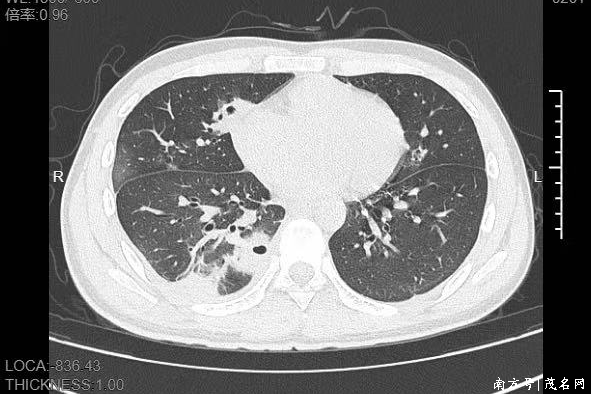

熬到第三天,小林已经烧到39℃,赶紧来到宁波大学附属第一医院就诊。接诊的呼吸与危重症医学科丁群力主任医师一看他的症状,立刻安排了CT检查。结果显示:小林的肺里有十几个空洞,部分肺组织已经坏死,这是典型的血源性肺脓肿。

像小林这样,当细菌跑到肺组织上后,就会开始疯狂破坏肺细胞,引发局部炎症。随着炎症加重,肺组织会逐渐坏死、液化,最终形成一个个空洞。

如果没有及时就医,风险还会持续升级,轻则导致肺脓腔破裂,引发脓胸、脓气胸,胸腔里积满脓液,重则细菌会再次扩散到肝脏、心脏等关键器官,甚至引发脓毒症休克,危及生命。

即便最终治愈,严重的肺组织坏死也可能留下后遗症,比如肺功能下降,影响后续的正常呼吸。